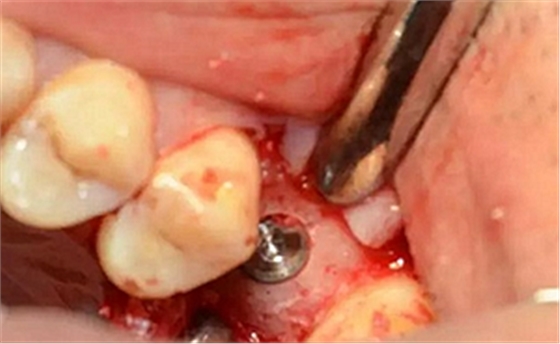

局麻后切開翻瓣

暴露骨面,輕柔處理軟組織

清理骨面和臨牙齦下結(jié)石及炎性肉芽組織

定點(diǎn)定向,初步擴(kuò)孔

使用止停環(huán)控制深度,逐級(jí)預(yù)備打開嵴頂入路。探之竇膜力反饋正常,呈持續(xù)張力。手動(dòng)探查分離通路周圍竇粘膜并略提升。

用配套工具進(jìn)行水壓式?jīng)_頂,提升竇膜。手感力反饋和回吸正常。在沖壓水量上要控制,緩慢反復(fù)多次抽吸,確保竇粘膜提升均勻。

逐次添加少量骨粉,加壓到位,反復(fù)進(jìn)行。骨粉總量約0.25g

植入種植體,注意方向控制和初期穩(wěn)定性。

上覆蓋螺絲